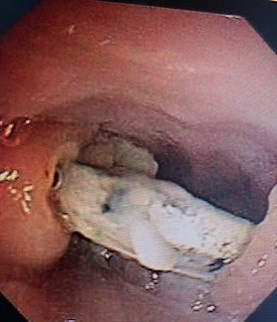

Trong quá trình nội soi thực quản, kíp mổ ghi nhận có dị vật xương 3 mảnh, dài nhất 1,5x4 cm ở vị trí đoạn dưới của thực quản, cách cung răng trên 25 cm, đâm xuyên thành, có mủ giả mạc trắng bám hoại tử niêm mạc, xì dò khí dịch mủ vàng đục nhiều và kết hợp mở cạnh cổ dẫn lưu dịch mủ.